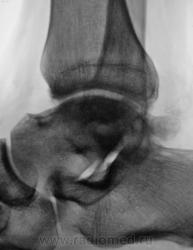

Пациент направлен на рентгенографию голеностопного сустава с диагнозом ДОА.

Похоже  на  остеохондропатию  блока  таранной  кости  +   ДОА.

А присутствует линейный (или лентовидный, я их путаю) остеопороз, а это признак острого процесса.

Будем думать, что некроз блока таранной кости не такой уж и асептический, какая-то инхвекция там есть.

Посттравматический артроз с кистовидной перестройкойлатерального мыщелка Субхондральное уплотнение исужение суст. щелей естьИ неконгруэнтность большеберцового эпифиза к таранной маленько просматривается?